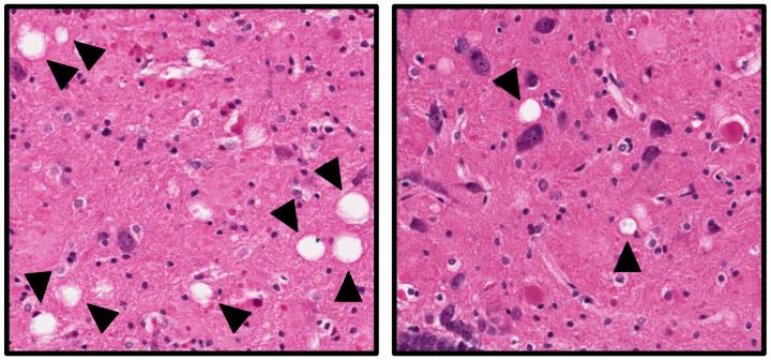

L'immagine mostra il tessuto cerebrale di ratti di Alzheimer che non sono stati trattati (a sinistra) o trattati (a destra) con il composto neuroprotettivo. I 'fori' bianchi indicati dalle frecce sono aree di morte delle cellule cerebrali e sono più numerose nei ratti non trattati. (Fonte: Pieper Lab, University of Iowa)

Il team ha anche esaminato i cervelli dei ratti ai due punti temporali. Hanno trovato che i segni tradizionali dell'MA (placche amiloidi, grovigli di tau e neuroinflammazione) erano notevolmente aumentati nei ratti di Alzheimer, indipendentemente dal fatto che fossero stati trattati con P7C3 o no. Tuttavia nel cervello dei ratti di Alzheimer che avevano ricevuto il trattamento P7C3 molti neuroni erano sopravvissuti.